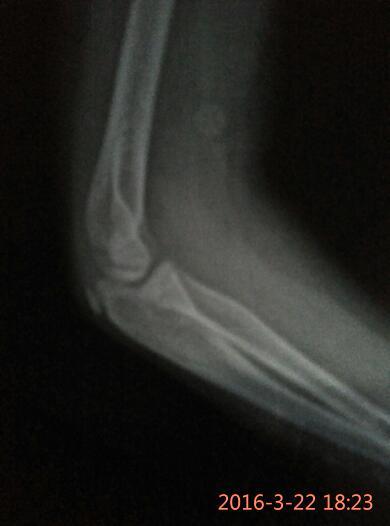

孩子胳膊摔伤,拍的片子,麻烦帮忙看看是骨头掉一块渣吗? 点击展开 两只猴子的妈妈 2016-03-22 18:29 满意回答 小孩子多大,鹰嘴那个位置痛吗,看起来不太像,要看症状才好说 cn#BfBVkBQufu 2016-03-22 18:31 宝宝知道提示您:回答为网友贡献,仅供参考。 相关问题 我脚是2个月前摔伤的,当时拍了片子,医生说骨头 宝宝胳膊摔伤拍过片子可以打预防针吗 我家孩子胳膊摔伤做过手术可现在己恢复3个月才只能弯曲70度怎么办拍过片子都正常